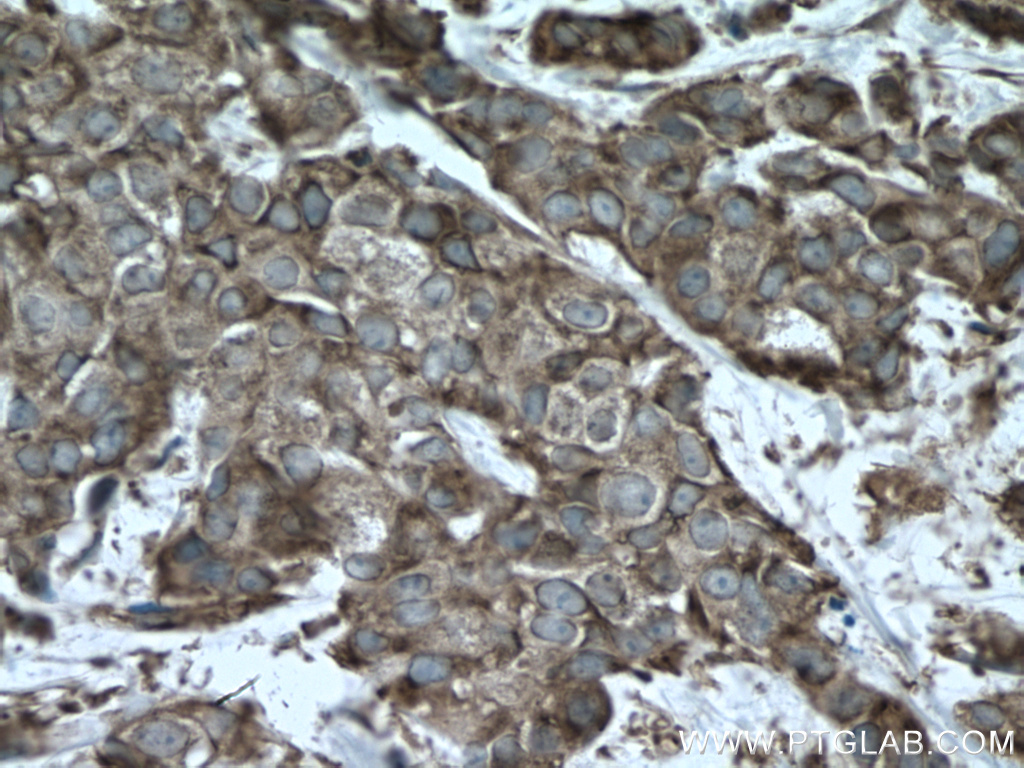

| Positive IHC detected in | human lung cancer tissue, human colon cancer tissue Note: suggested antigen retrieval with TE buffer pH 9.0; (*) Alternatively, antigen retrieval may be performed with citrate buffer pH 6.0 |

| Immunohistochemistry (IHC) | IHC : 1:50-1:500 |